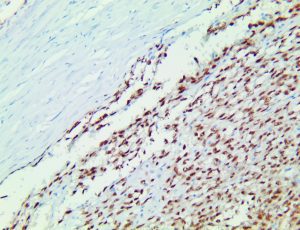

It is the ICU physician who is most likely to witness one of the deadliest manifestations of the abnormal immunological response, the cytokine storm syndrome (CSS). This response is also referred to by some as the cytokine release syndrome (CRS). CSS is characterized by continuous activation and expansion of macrophage and lymphocyte populations, which secrete large amounts of cytokines, causing the cytokine storm. This massive cytokine release is akin to hemophagocytic lymphohistiocytosis (HLH) disease, a syndrome characterized by initial unchecked and persistent activation of cytotoxic T lymphocytes and NK cells.

Clinical and laboratory manifestations of HLH include fever, enlarged liver and/or spleen, neurologic dysfunction, coagulopathy, liver dysfunction, cytopenias (i.e., low levels of erythrocytes, leukocytes, and/or platelets), hypertriglyceridemia, hyperferritinemia, hemophagocytosis, and eventually diminished NK cell activity as the immune system becomes progressively paralyzed. HLH can be familial (primary HLH) or secondary to another disease process (sHLH), such as rheumatic disease, in which it is referred to as macrophage activation syndrome (MAS, characterized by elevated ferritin).